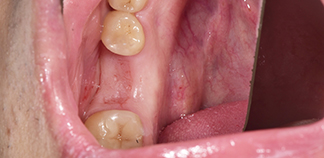

До лечения

Жалобы на эстетику зубов.

Пациенту 46 лет.

Как лечили

Проведено препарирование четвертого и пятого зуба с последующей фиксацией постоянных коронок.

Лечение проведено в течение одной недели.